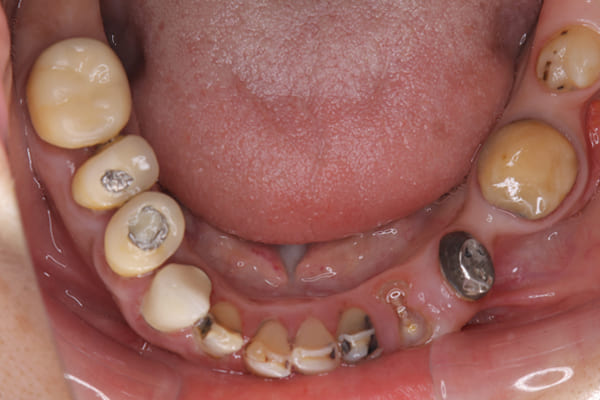

下顎治療前

-

治療前の入れ歯の奥歯は、治療後の義歯と比較しても分かるように、歯が削れ平らになった状態です。

これにより奥歯のかみ合わせは低くなり、前歯のみが強くあたり、かみ合わせにより上の前歯大きな負担がかかっていたことにより、上の前歯が折れたことが考えられます。